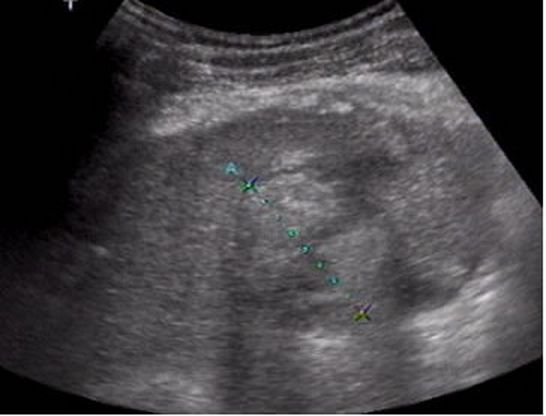

Neoplasias malignas primarias Módulo satélite (flecha). Carcinoma hepatocelular con aguja |